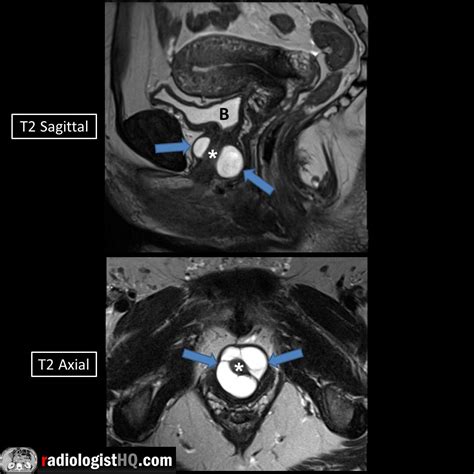

Diagnosis requires a high index of suspicion, especially when standard treatments for UTIs fail. A physician will typically perform a physical exam, which may reveal a tender mass along the anterior vaginal wall. If pressure is applied to the mass, it is not uncommon for a small amount of urine or purulent discharge to exit the urethra.

MRI (Magnetic Resonance Imaging) The gold standard for visualizing the size and location of the diverticulum.

Voiding Cystourethrogram (VCUG) Uses contrast dye to see if the pouch fills during urination.

Urethroscopy Direct visualization of the urethra using a thin camera to locate the diverticular opening.